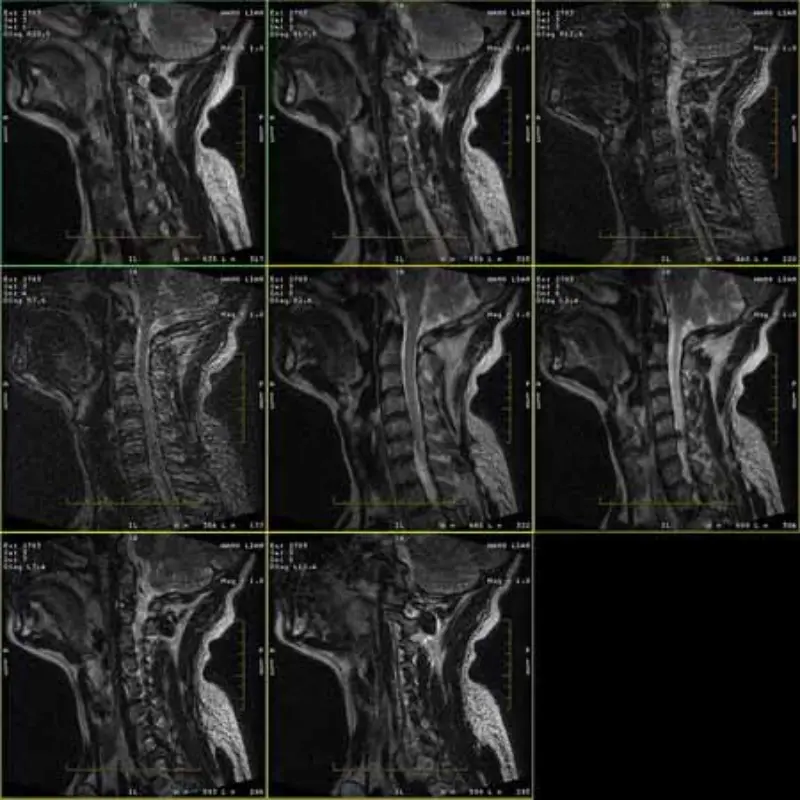

As imagens dos protocolos FRFSE e GRE apresentam fantasmas e, às vezes, imagens de SNR baixo aparecem em uma série. Mas as imagens do protocolo SE são normais.

Por favor, veja anexar imagens.